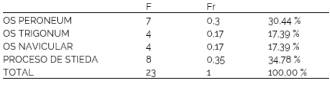

Del total de pacientes relevados por el estudio se encontró presencia de huesos accesorios en el tarso en el 9,58% de los casos constituyendo un grupo de 23 pacientes, mientras que 217 no presentaron alteraciones (90,42%). Las variantes encontradas en el 9,58% de la muestra fueron presencia de OT fusionado al proceso lateral del astrágalo (PS) en 3,33% del total, OT sin fusionar 1,66%, ON 1,66% y OP en 2,93%. (Tabla 1)

El PS fue la variante anatómica de mayor presencia en la investigación llegando al 34,78% del total de variantes encontradas, alcanzando el 52,17% si se asocia al hallazgo de OT dada su etiología común. La aparición de OP representó el 30,44% de los hallazgos mientras que la variante con menor extensión fue la de ON con 17,39% del conjunto de los pacientes con huesos accesorios tarsianos. (Tabla 1a).